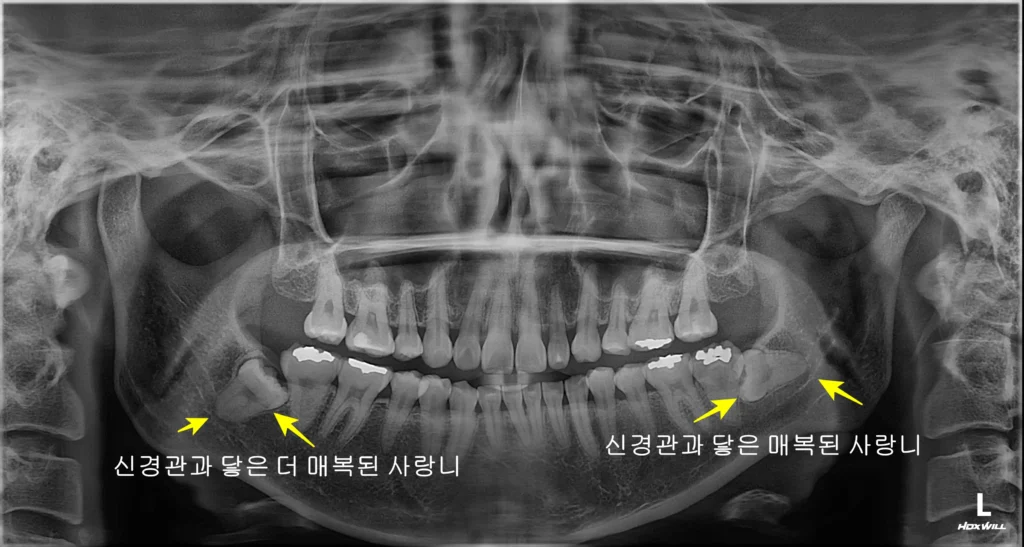

환자분께서는 왼쪽 아래 사랑니 부위가 붓고 통증이 심해 내원하셨습니다.

아픈 사랑니 (왼쪽 아래)

안 아픈 사랑니 (오른쪽 아래)

반대편에는 당장 아프지 않은 매복 사랑니가 있었습니다. 하지만 아프지 않다고 방치하면 다음과 같은 문제가 생길 수 있습니다.

결국 환자분은 현재 아픈 사랑니뿐만 아니라, 잠재적 위험이 있는 반대편 매복 사랑니까지 모두 발치하기로 결정했습니다.